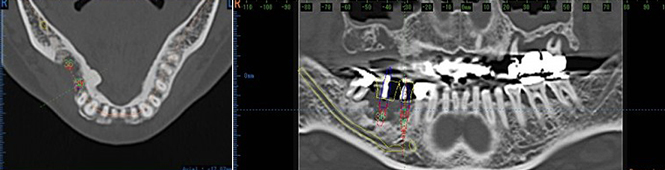

インプラント治療は、術前の確実な診断が必要です。

当院では、すべての症例にCT撮影を行い、最新の診断・分析を行ってから、インプラント治療を行います。

さまざまな角度から診ることにより、

確実で安全なインプラント治療が行えます。